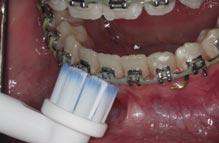

The placement of fixed attachments and auxiliaries upon a tooth surface increases the risk of plaque accumulation ( Figure 1 ). This occurs through disruption of the oral cavity’s natural self-cleaning mechanism, and such appliances act as both a barrier to oral hygiene and local retentive factors, thereby hindering hygiene practices.1

Several studies have investigated the efficacy of manual and electric toothbrushes (Figures 2a and 2b). Some authors have found electric to be more effective than manual models,5 while others could not reproduce these conclusions. Conversely, the opposite has also been demonstrated.6 A recent systematic review and meta-analysis on this topic emphasised the equivocal nature of the current evidence.7 Various manual toothbrush designs have also

been investigated (Figures 3a and 3b). Research has found no significant difference in plaque removal effectiveness between different manual designs.8 There is some evidence that new models of electric toothbrushes may be more effective than traditional ones.

The current consensus is that there is insufficient evidence to advocate for the use of electric over manual toothbrushes, or for any one manual design, for improving plaque control in FA patients. Therefore, the dental team should aim to improve patients’ knowledge and awareness, in conjunction with other aids, rather than focusing on the type of brush used.